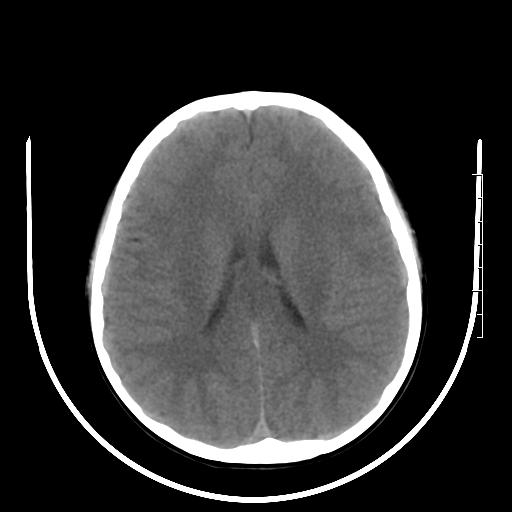

标题: PED3377:m、9y,恶心、呕吐,每月发作2-3次。 [打印本页]

标题: PED3377:m、9y,恶心、呕吐,每月发作2-3次。

颅脑ct轴位平扫颅内未见明确异常。

右侧基底节区见钙化灶

右侧壳核多枚点状钙化灶。去请结合临床。

头颅ct平扫未见异常

颅脑ct平扫未见异常。

右侧壳核多枚点状钙化灶,请结合临床。

右侧壳核多发钙化灶,请结合临床。